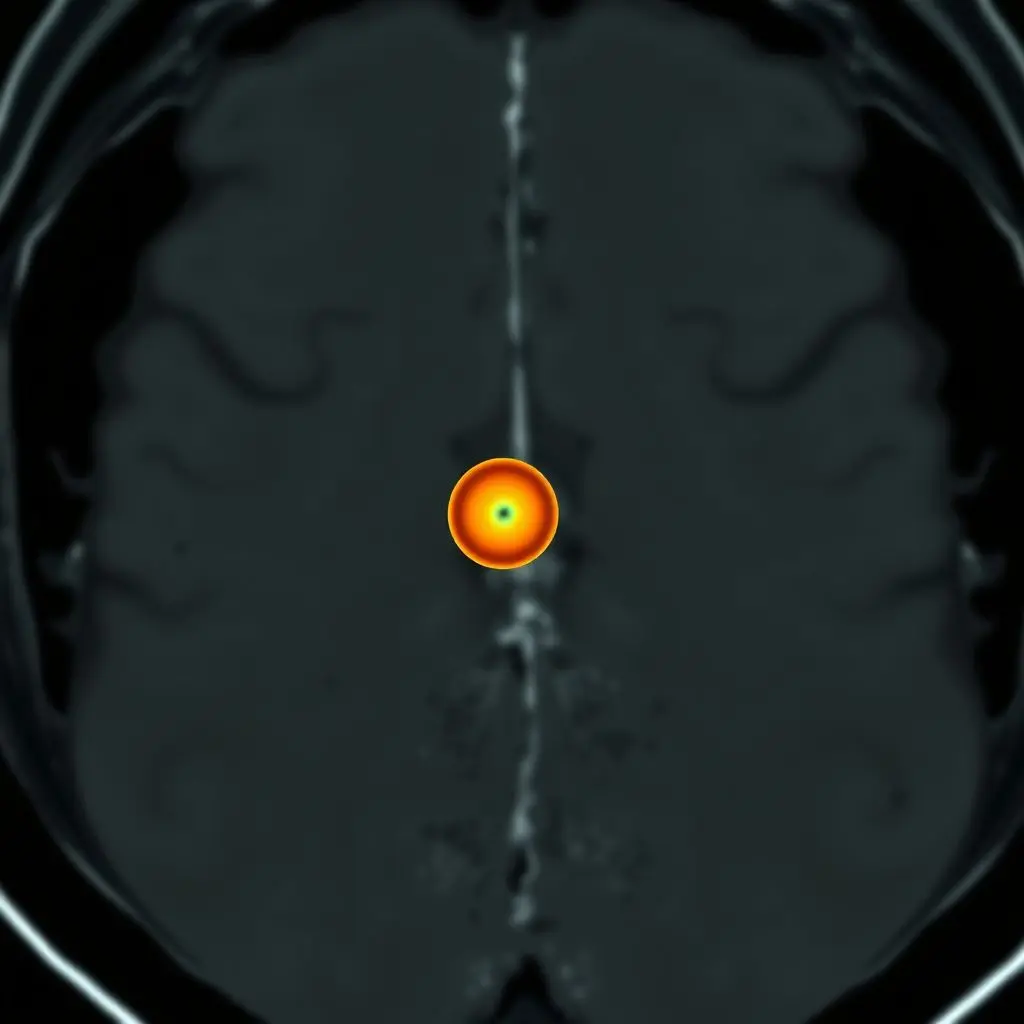

Medical scans—MRIs, CTs, X-rays—are treasure troves of data. They capture incredible detail about our internal landscape. But within that vast ocean of information, finding those *tiny*, early warning signs, say, a microscopic tumor just beginning its journey, is incredibly tough. It’s a task that demands extreme focus, experience, and frankly, a bit of luck, even for the most seasoned medical experts. Early detection is often the key to successful treatment and survival, but finding that ‘needle in a haystack’ early on has always been a significant challenge.

That’s exactly where Artificial Intelligence is stepping in, promising to revolutionize how we approach proactive health and disease diagnosis. Think of AI as giving doctors not just a helping hand, but a kind of ‘superhero vision’. If the idea of AI seeing the unseen blew your mind, you might want to see this quick visual take on it:

Crucially, AI can process and analyze every single pixel and its relationship to surrounding pixels across an entire scan volume simultaneously and consistently, something impractical for a human. It can pick up on micro-calcifications in mammograms too small to be immediately obvious, detect subtle lung nodules on CTs that might be missed on first pass, or identify early signs of neurological conditions in brain MRIs.